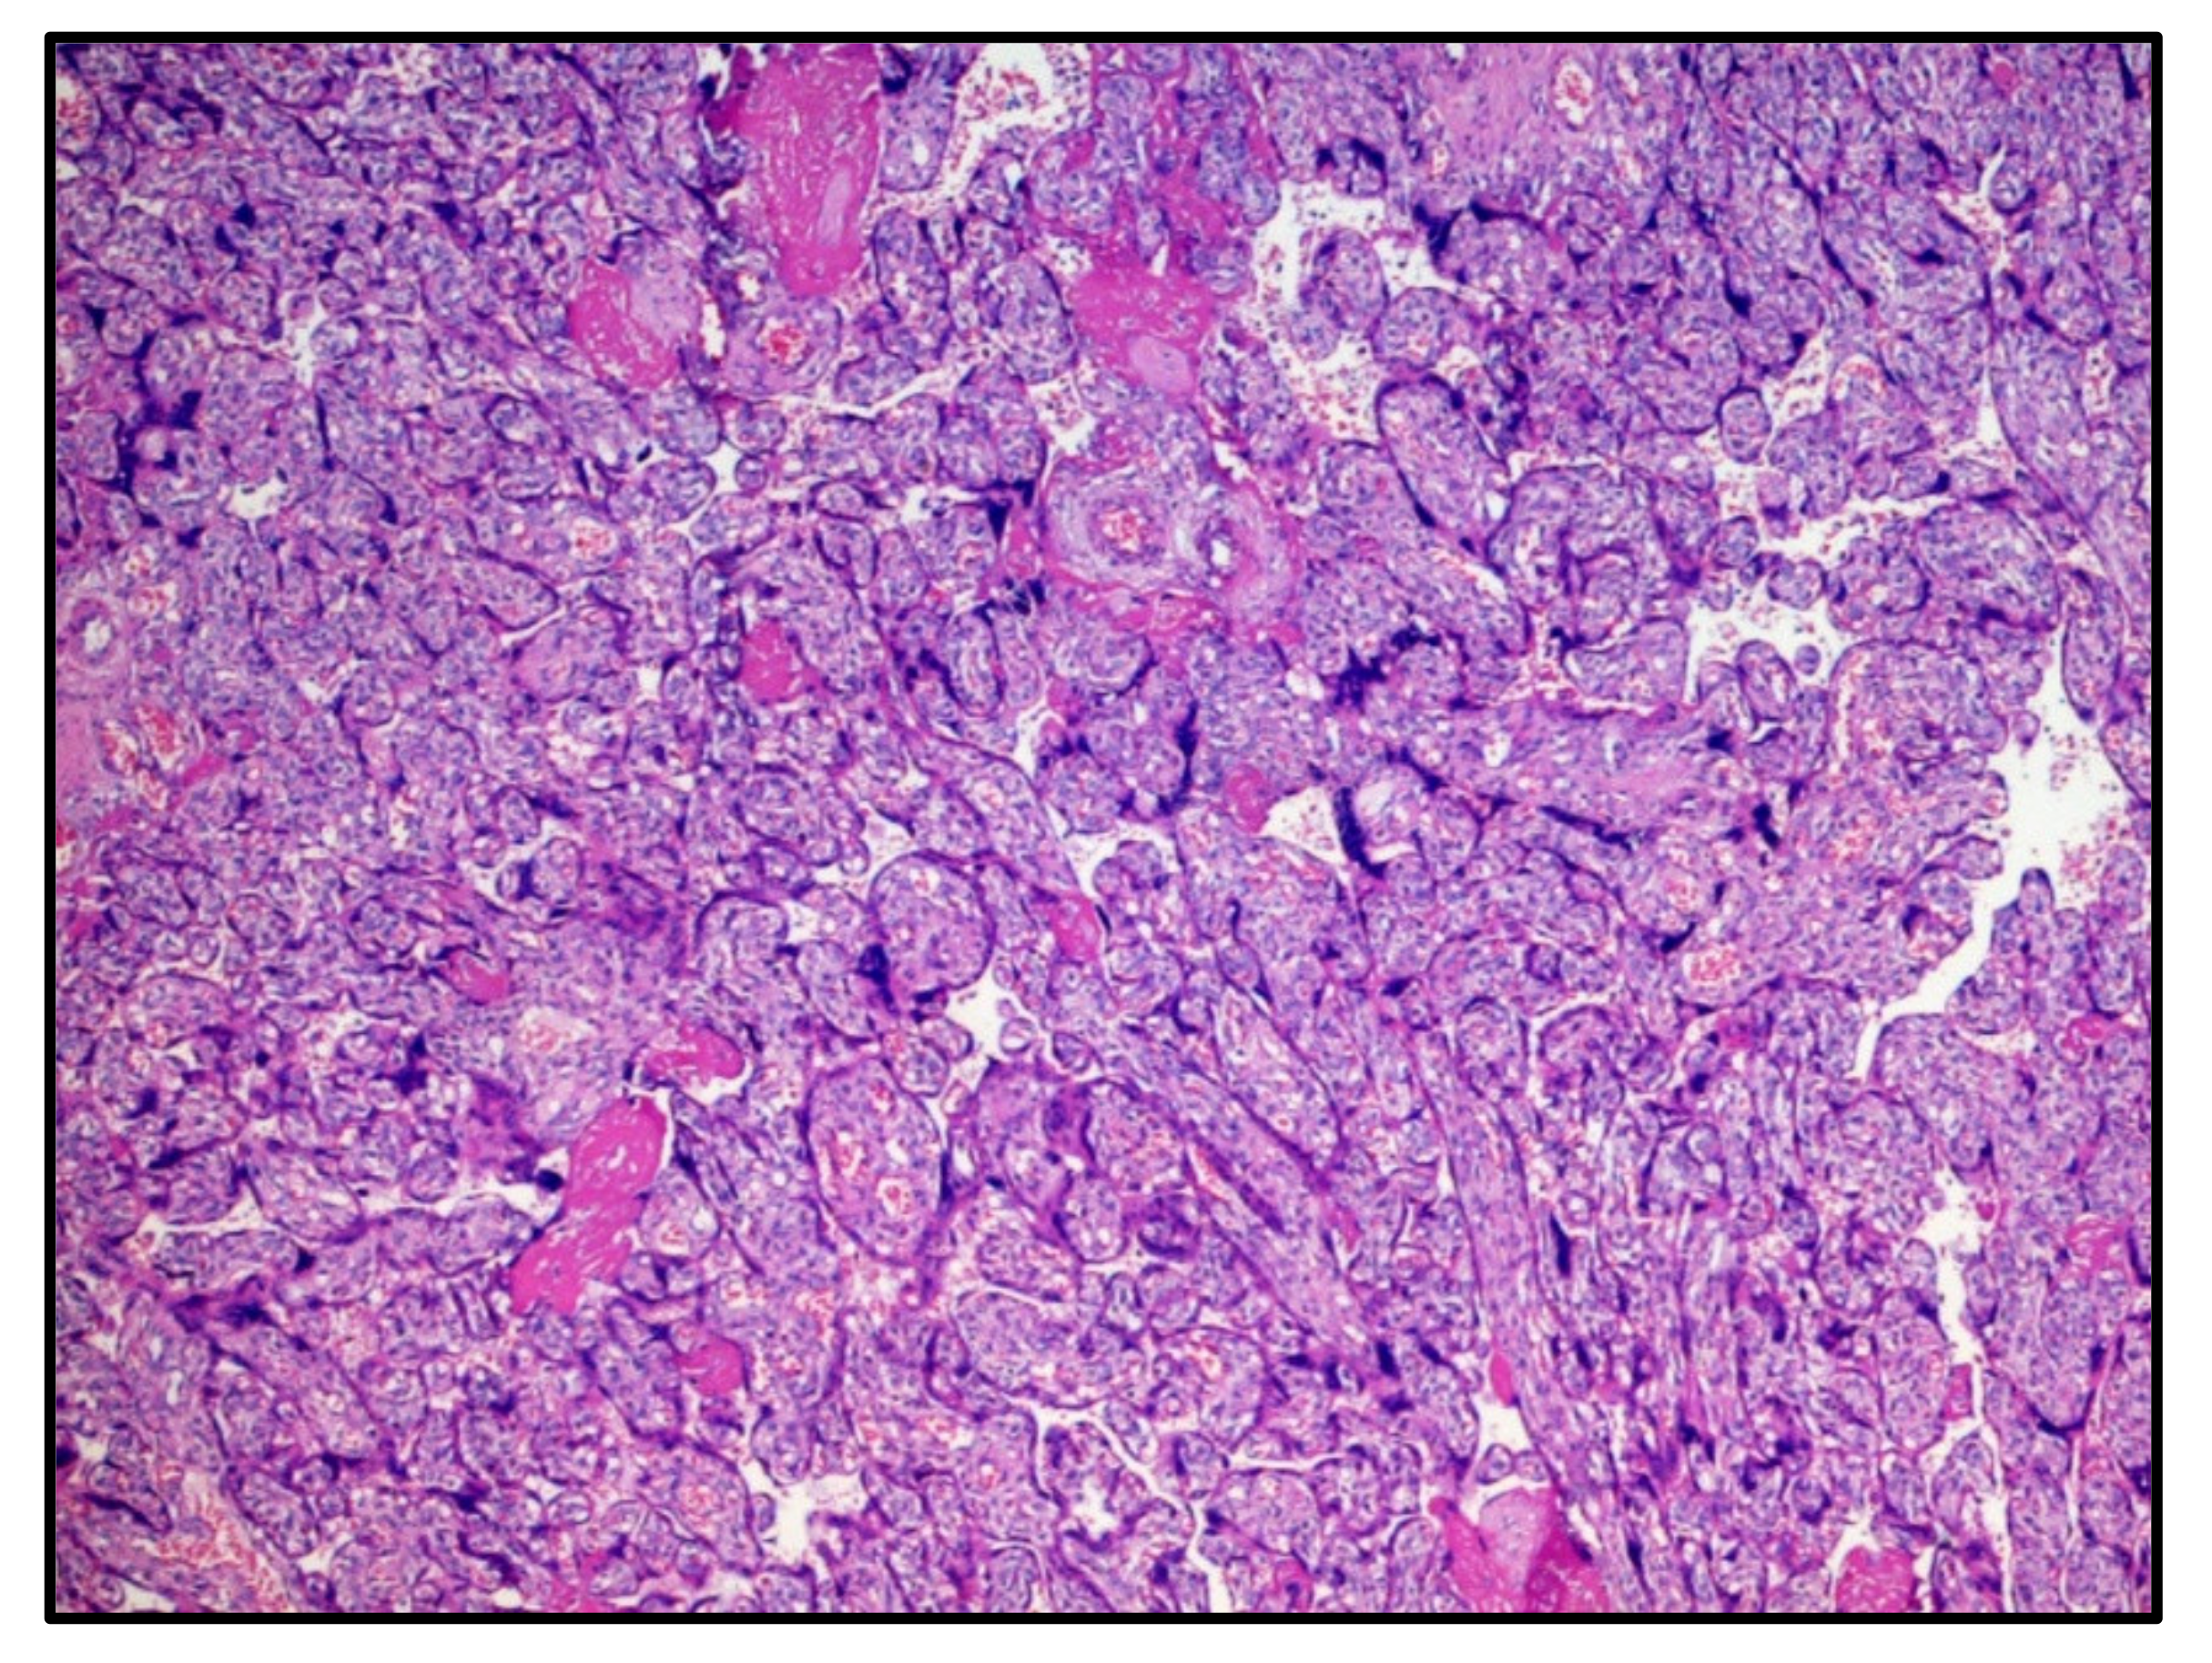

The first chorionic disc corresponded to the gestational age and presented very large areas of intervillous fibrinous deposition (Figure 1) with the presence of numerous perivillary histiocytes. Minor recent infarct foci were also described, while umbilical cord and amnio–chorionic membranes were completely normal. The immunohistochemical reaction for the SARS-CoV-2 protein S1 was strongly expressed both in the syncytiotrophoblast cells and in the perivillary histiocytes described in H&E (Figure 2).

Figure 1. Histological features of the first chorionic disc: deposition of intervillous fibrin and chorionic villi corresponding to the gestational age (30 weeks). Hematoxylin-Eosin, 10×.

Figure 2. Immunostaining for anti-SARS-CoV-2 spike protein S1 positive at the level of the syncytiotrophoblast and perivillary histiocytes. (IHC, Original Magnification: 10×).